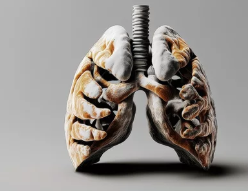

간질성 폐질환(Interstitial Lung Disease, ILD)은 **폐 조직(간질, Interstitium)**에 염증과 섬유화가 생겨 폐 기능이 점점 저하되는 질환입니다.

간질성 폐질환은 폐포(공기가 드나드는 작은 공기 주머니)와 폐혈관을 둘러싼 조직(간질, Interstitium)에 염증이 생기고 점차 섬유화(Fibrosis)로 진행되는 질환입니다.

- 폐 조직이 딱딱해지고(섬유화) 폐가 산소 교환을 원활하게 하지 못함